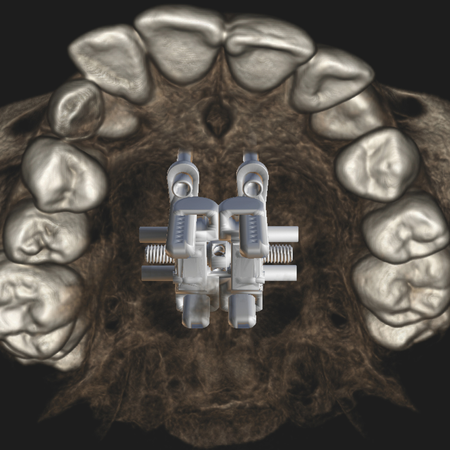

Avanços na expansão rápida da maxila: comparação de técnicas e impacto na precisão e qualidade do tratamento

OBJETIVO: O presente estudo visou delinear um panorama abrangente das técnicas de expansão maxilar, desde os métodos pioneiros até as abordagens contemporâneas. Para isso, foram considerados aspectos tais como: diagnóstico por imagem, planejamento digital, variações anatômicas e os diversos designs de dispositivos de ancoragem esquelética (MARPE – Mini-implant assisted rapid palatal expansion). MÉTODOS: A seleção dos estudos foi realizada em ordem cronológica, permitindo uma...

Advances in rapid maxillary expansion: comparison of techniques and impact on treatment precision and quality

OBJECTIVE: This study aimed to provide a comprehensive overview of maxillary expansion techniques, from the pioneering methods to contemporary approaches. This included aspects such as diagnostic imaging, digital planning, anatomical variations and the various designs of skeletal anchorage devices (MARPE - Mini-implant assisted rapid palatal expansion). METHODS: The studies were selected in chronological order, allowing a progressive and broad understanding of the advancement of the...